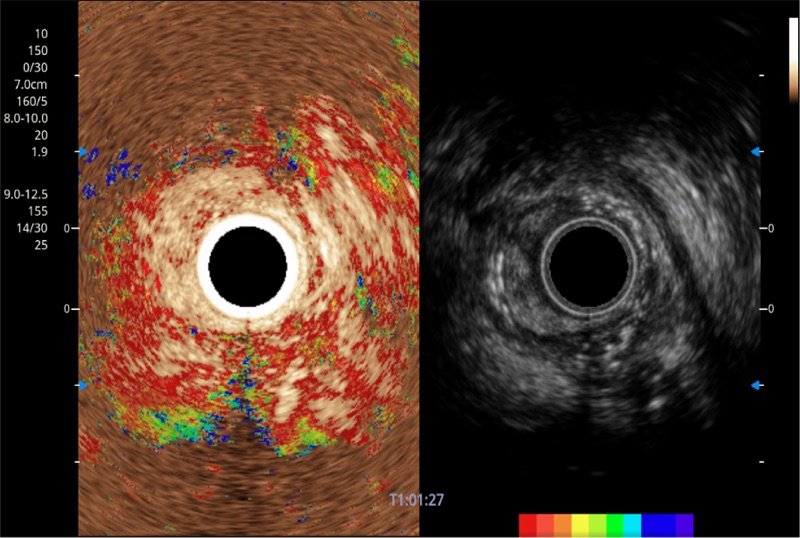

TIC时间强度分析曲线

具有四种造影成像效果